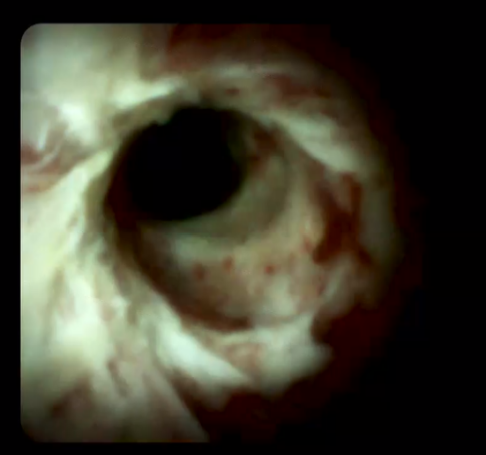

另外,經(jīng)口膽道子鏡光纖直視系統(tǒng)(SPYGLASS)是一種電子膽道子鏡,可通過十二指腸鏡到達(dá)膽管或胰管內(nèi),對病變進(jìn)行直視觀察,高清高分辨率顯示病變、并精準(zhǔn)指導(dǎo)活檢,對于膽胰管狹窄的診斷治療具有重要意義。

259842c0b1ad45318354e54fe46ec3e0.Png   a002b78cca244f27bc594941e601792b.Png

經(jīng)口膽道鏡下膽管組織活檢